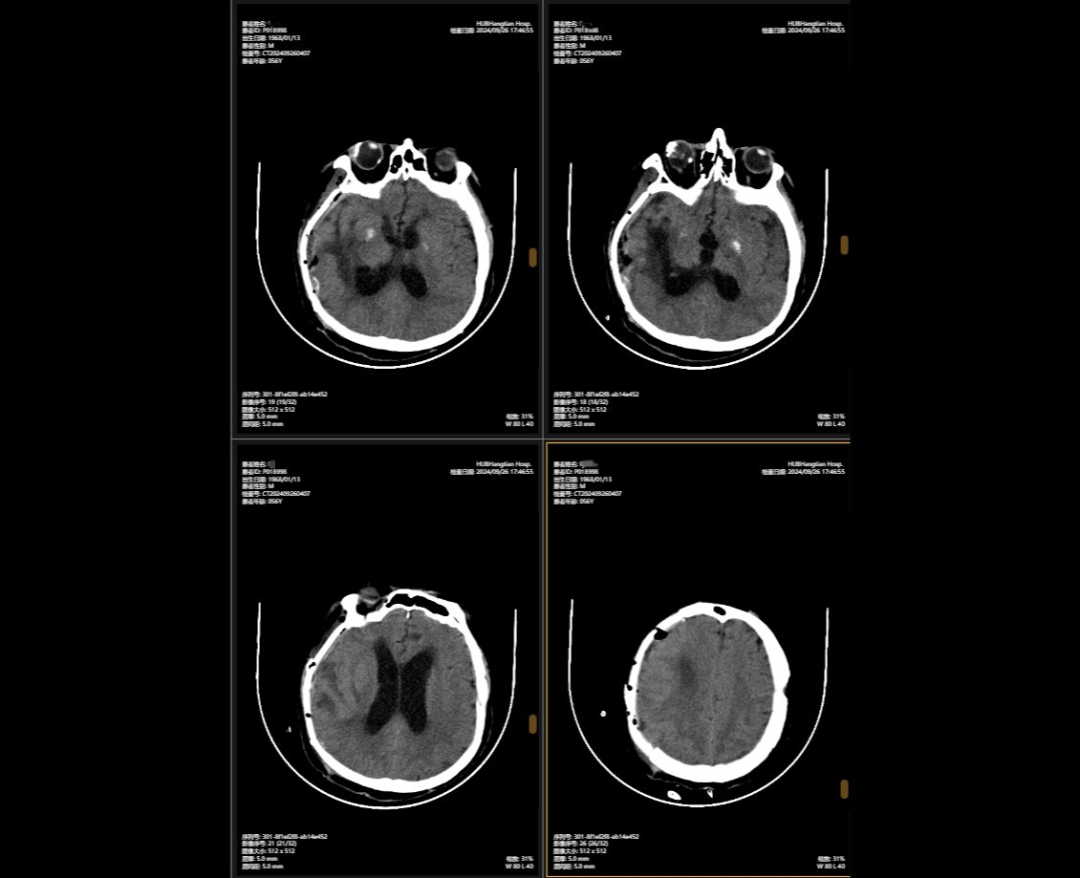

2024年5月,56歲的李先生(化名)不幸遭遇嚴重車禍,當場昏迷,生命垂危。他被緊急送往湖北航天醫(yī)院后,檢查結果讓所有人心頭一緊:他的頭部受到嚴重撞擊,不僅有多處出血,腦組織也有挫傷,甚至連呼吸心跳的“總司令部”——腦干都受了傷。除此之外,還有顱骨、頸椎和多處肋骨骨折,情況萬分危急。

李先生頭部的多處損傷就像一顆顆“炸彈”,隨時可能危及生命。航醫(yī)神經外科團隊接診后,面對如此復雜的顱內損傷,神經外科主任陳義勇當機立斷,一方面做好周密的手術準備,一方面迅速展開多學科會診,多學科團隊緊急集合,反復協(xié)商探討,一同制定了詳盡手術方案。手術方案確認后,神外團隊爭分奪秒,第一時間為李先生實施了顱內多發(fā)血腫清除術+右側開顱顱內減壓+去骨瓣減壓術+左側硬膜外血腫清除術+矢狀竇破裂止血術。手術過程中,醫(yī)生們精準操作,成功止住了出血,最大限度地保護了正常腦組織,為李先生贏得了生的希望。

顱骨缺損修補術前術后對比